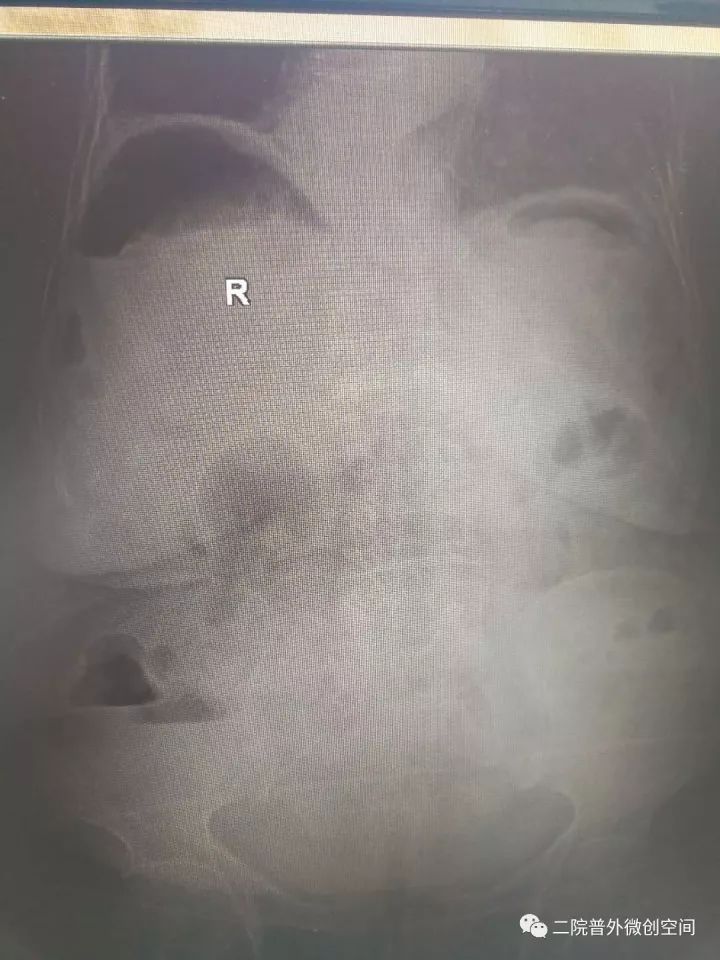

据悉,老奶奶月前摔伤而口服止痛药,2017年10月23日中午突然出现腹痛,逐渐加重,急到当地卫生院就诊,当地医生检视后考虑“急腹症”急转夏邑县第二人民医院普外科。入院后经副主任医师井晓亮检查后考虑消化道穿孔,治疗需手术治疗。

经过充分的术前准备,在麻醉科同事保驾护航下成功为患者施行了腹腔镜下胃穿孔修补术。麻醉及手术过程的艰难程度可想而知——低血压、低血氧、腹腔充满脓液,穿孔大......而这些,在井晓亮主任、谢龙医师、王天琪医师的精细操作下一一化解!